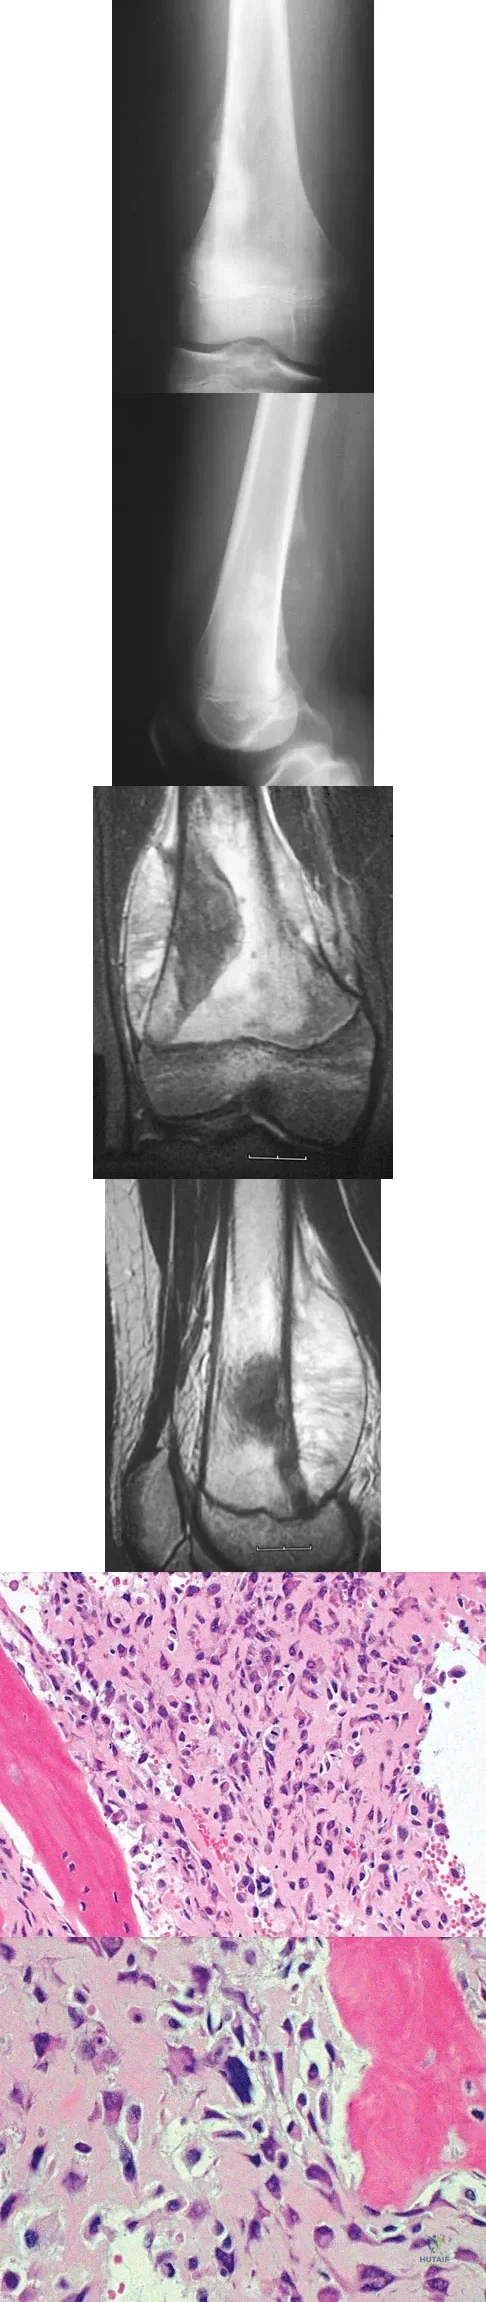

Figures 6a through 6d show the radiographs and biopsy specimens of an 8-year-old girl with leg pain. Management of the lesion should consist of

Explanation

The biopsy specimens show a chondromyxoid fibroma with varying amounts of cartilage, benign fibrous tissue, giant cells, and loose myxoid areas. Chondromyxoid fibroma is a benign active bone lesion that is best treated with aggressive curettage and bone grafting. Although recurrences are common, more aggressive treatment is not warranted initially. Wilson AJ, Kyriakos M, Ackerman LV: Chondromyxoid fibroma: Radiographic appearance in 38 cases and in a review of the literature. Radiology 1991;179:513-518.

A 13-year-old boy has knee pain after sustaining a mild twisting injury while playing basketball 4 weeks ago. Radiographs and MRI scans are shown in Figures 24a through 24d, and biopsy specimens are shown in Figures 24e and 24f. Treatment should consist of

Explanation

The imaging studies and histology are consistent with high-grade osteosarcoma. The standard treatment for osteosarcoma is neoadjuvant chemotherapy combined with wide surgical resection that can be performed with amputation or limb salvage depending on characteristics unique to each tumor and each patient. In most patients, limb salvage surgery can be performed with reconstruction using allografts and/or megaprostheses. Osteosarcoma is poorly responsive to radiation therapy. Chemotherapy alone, in the absence of appropriate surgery, has not proven effective. Simon MA, Springfield DS: Surgery for Bone and Soft-Tissue Tumors. Philadelphia, PA, Lippincott-Raven, 1998, pp 265-274.